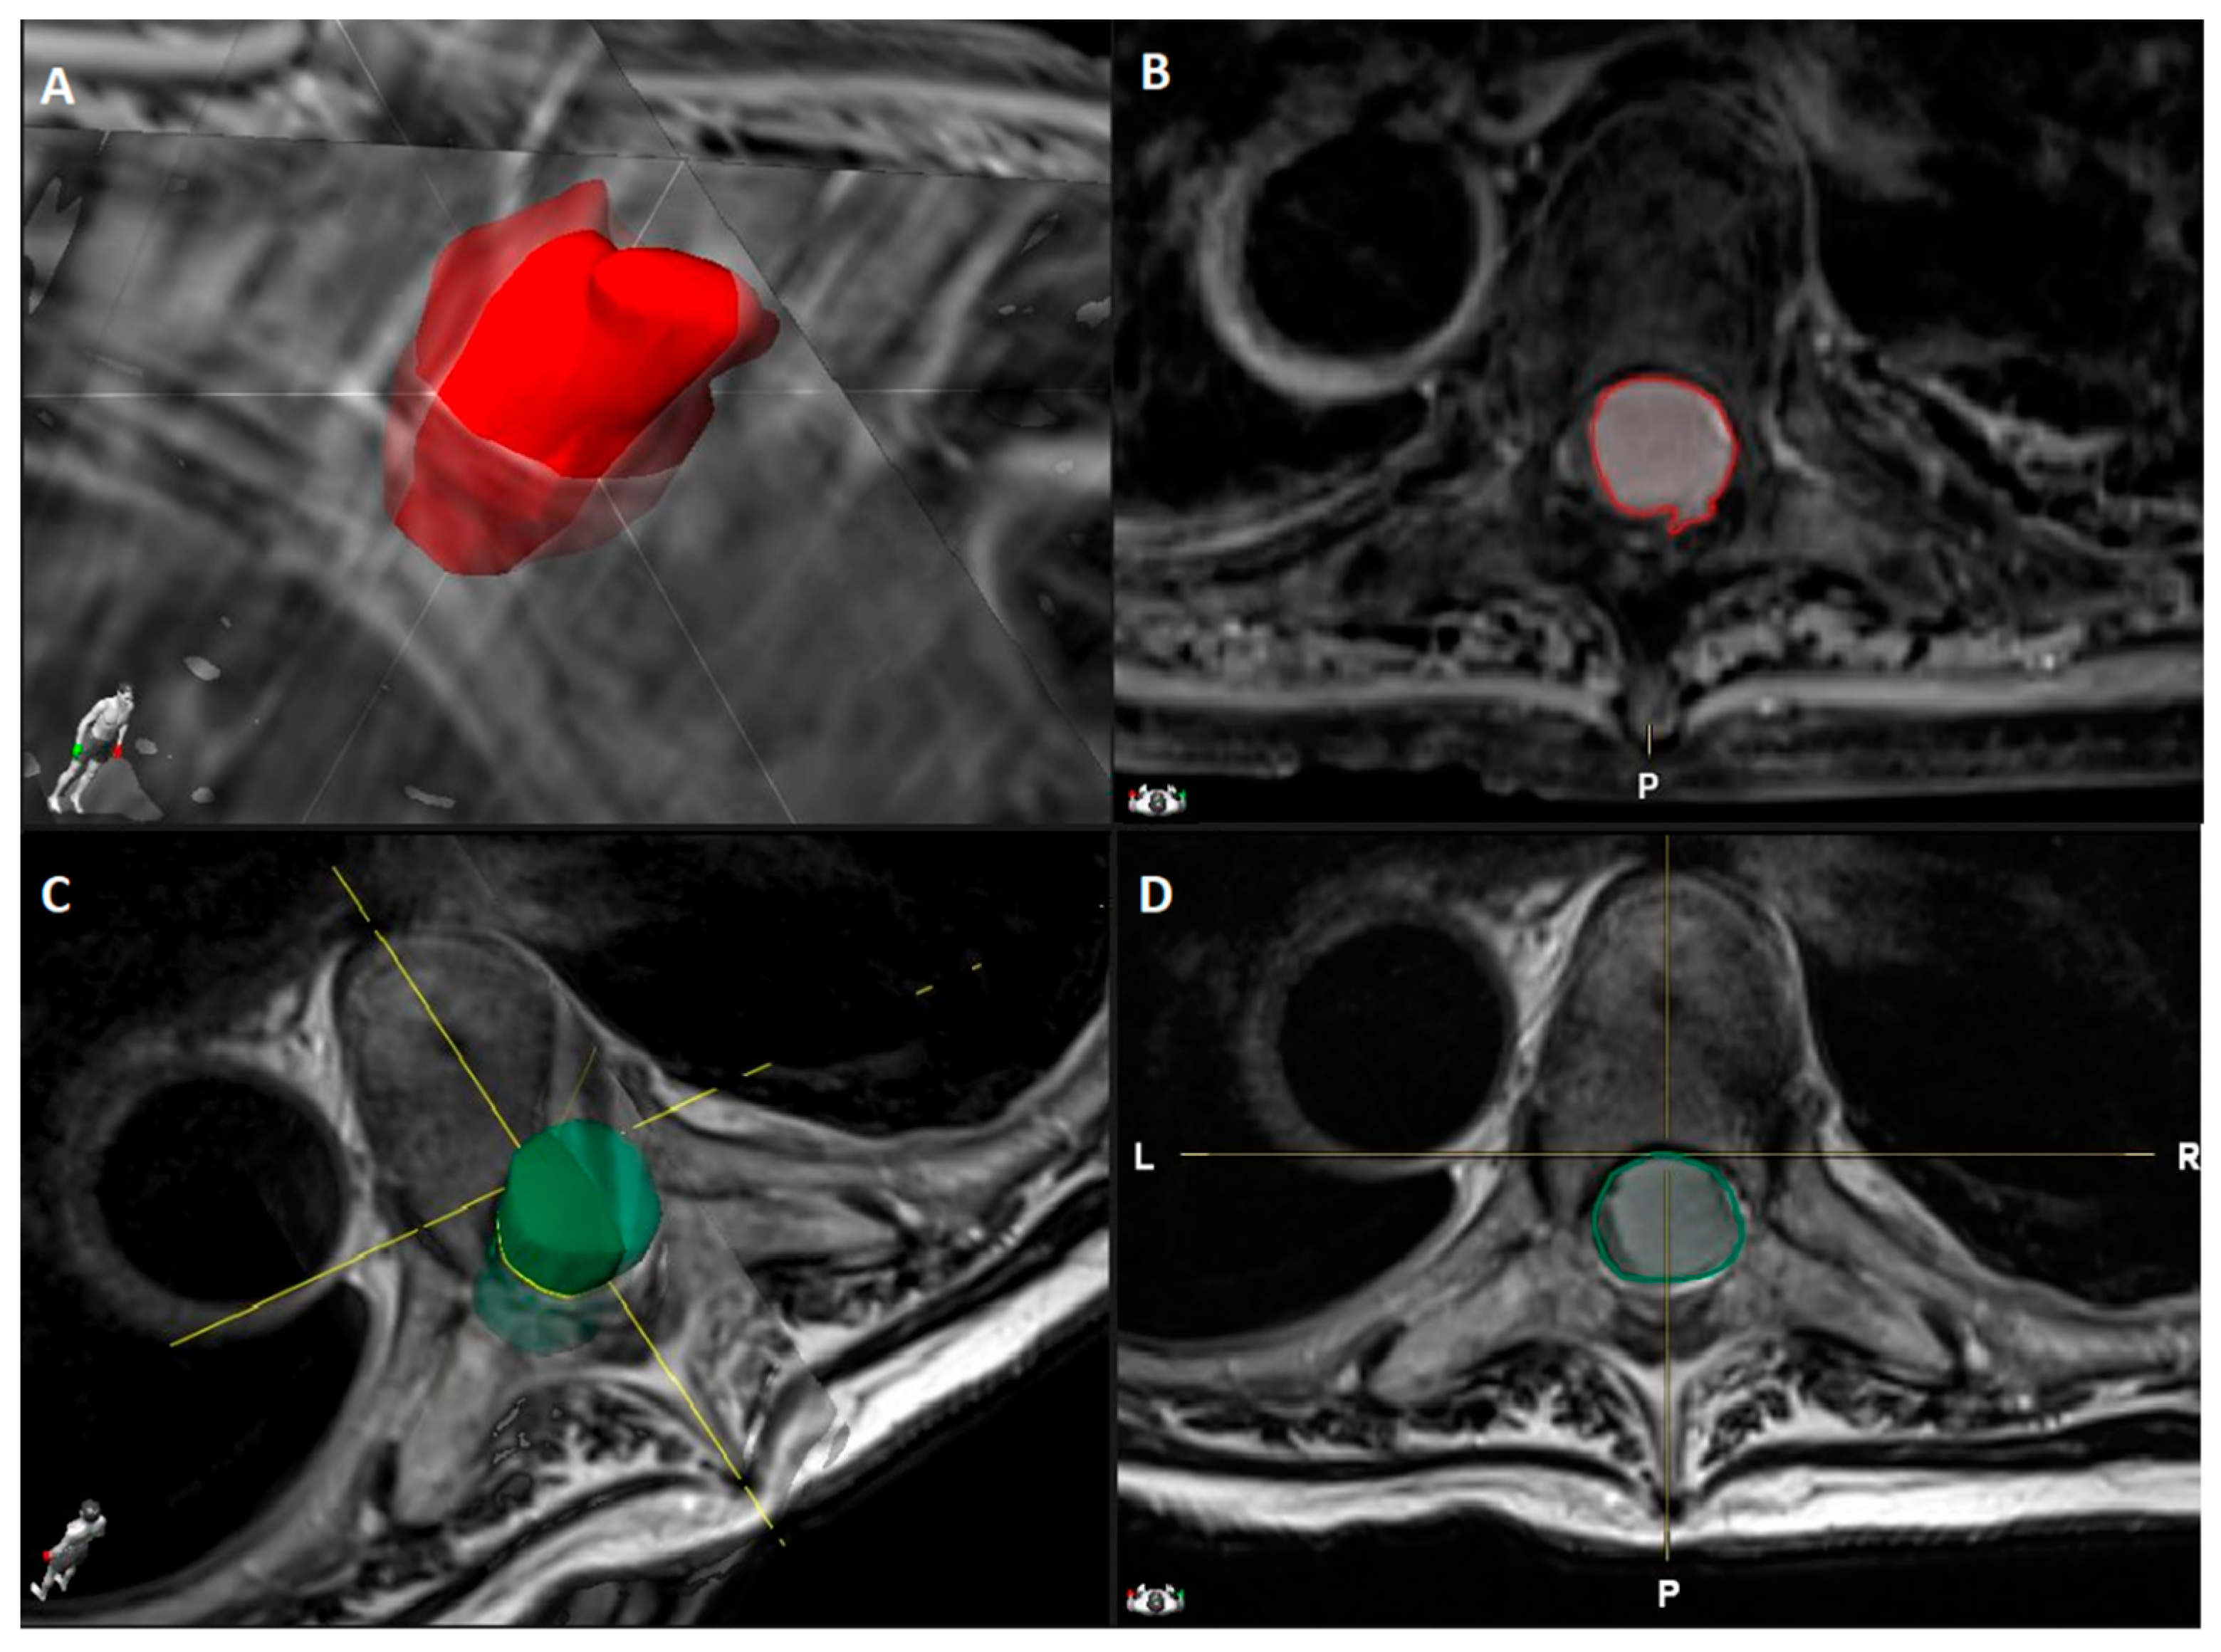

- Tumor volume (cm3) manually segmented using Brainlab Elements® on axial T1- weighted images with contrast (slice thickness from 3 to 4 mm) (Figure 1).

Figure 1. Dorsal Th5-Th6 WHO grade I meningioma with anterior dural attachment: (A) 3D tumor volume rendering (2.6 cm3) obtained by (B) tumor segmentation on axial T1-weighted MRI images after contrast administration using Brainlab Elements®; (C) Spinal canal volume rendering (3.5 cm3) obtained by (D) spinal canal segmentation on axial T2-weighted MRI images using Brainlab Elements®. - Canal volume (cm3) manually segmented using Brainlab Elements® on axial T2- weighted images (slice thickness from 3 to 4 mm) to assess the volume of the corresponding spinal canal segment (identified by the segment between two axial slices corresponding to the upper and lower limits of the meningioma) (Figure 1).